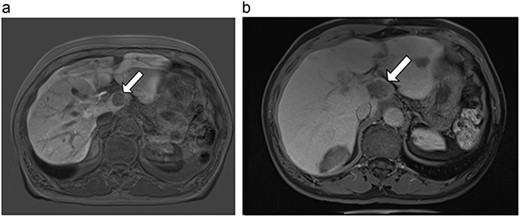

(a) Pre-ablation MRI demonstrating 5 mm lesion in caudate lobe of liver. (b) Post-ablation MRI (19 days postoperatively) demonstrating 36.2 mm complete ablation of caudate lesion.

| 3 (5a,b) | 68, F | Colon adenocarcinoma | 6 cycles modified FOLFOX-6 | 8 | Laparoscopic microwave ablation and low anterior resection of colon | 5 | 36.2 | 31.2 | 15 | No |